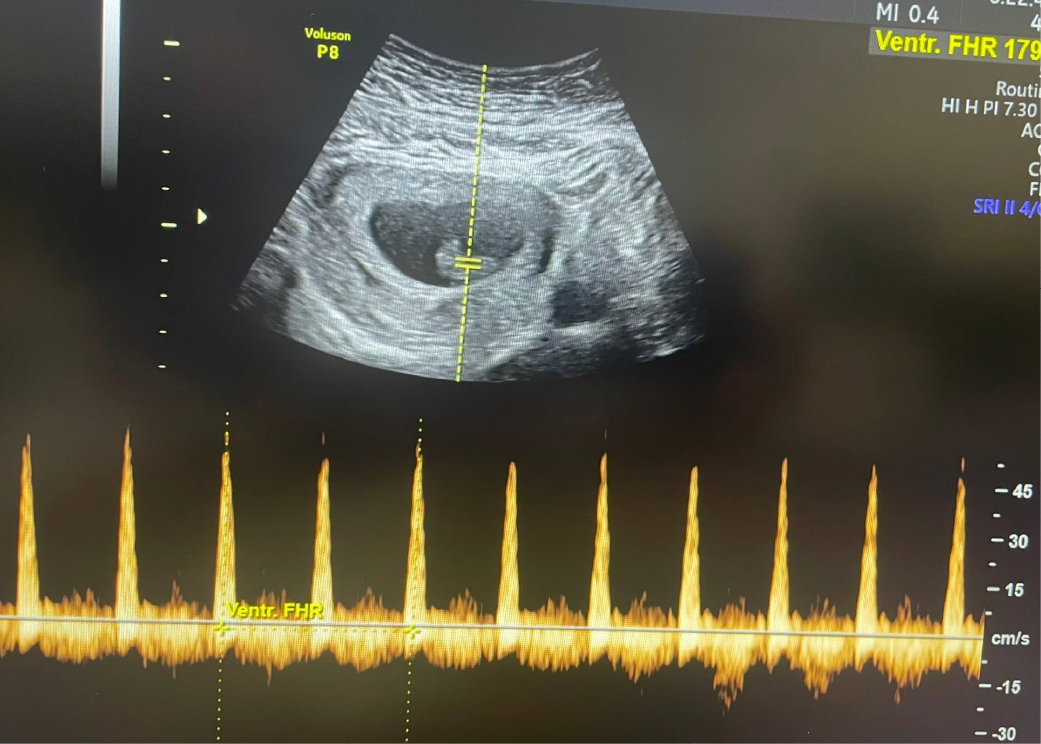

目前已來到8+周心跳活力好棒棒💖